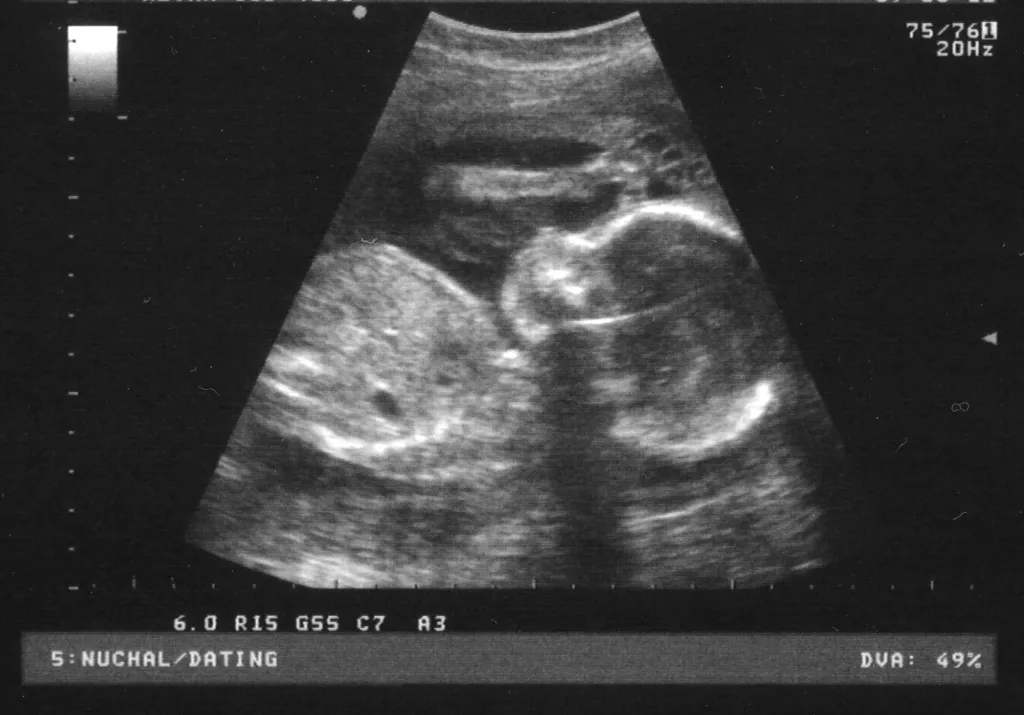

V naši ambulanti se predvsem trudimo, da bi imeli čimbolj profesionalen, diskreten in strokoven pristop k problematiki, ki jo obravnavamo. Da pa bi našim pacientkam zagotovili le najboljše, se nenehno izobražujemo in skušamo dosledno slediti sodobnim smernicam, ki se izoblikujejo tako pri nas kot tudi v tujini. Zato je med drugim na voljo tudi 3d 4D UZ - oziroma ultrazvočni pregled ploda.

V sklopu svoje ambulante ponujamo ginekološko in porodniško dejavnost, poleg tega svojim pacientkam nudimo preglede dojk in različne oblike ultrazvoka. Samoplačniško izdelamo tudi 3D 4D UZ.